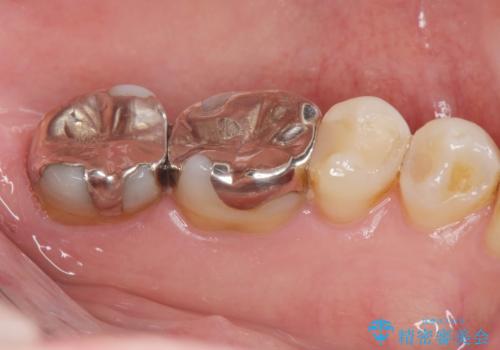

- 「長年使っている奥歯の目立つ銀歯を白くしたい。」、と希望され来院されました。

銀歯を丁寧に除去し、このように銀の覆っている面積が多い場合は、インレータイプではなくより強度に優れ歯もセラミックも長持ちするジルコニアクラウンでの治療を計画します。

- 26.4万円(ジルコニアクラウン×2・仮歯×2)費用は治療当時の料金となります